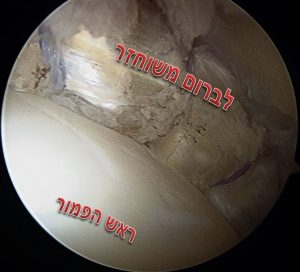

בתחילת הארתרוסקופיה המנתח סוקר את המפרק כולו באופן שיטתי, בשלב הזה ניתן להתרשם מאופי הפציעה הלברלית ומאיכות הרקמה הרכה שנשארה. אם הלברום איבד מהגמישות שלו ונמצא מסוייד כולו, במקרים של קרעים מורכבים בלברום או במקרים שבהם הלברום קטן מאוד ולא ניתן לתפירה – ניתן לשקול שחזור של הלברום. גם במקרים שבהם ניתוח ארתרוסקופיה של הירך לא הצליח ויש צורך בניתוח חוזר ההמלצה היא לבצע שחזור של הלברום ולא לנסות לתפור בשנית את אותו הלברום.

את הלברום משחזרים בעזרת שתל גיד שמוכנס למפרק דרך הפורטלים של הניתוח ומקובע למקומו בעזרת עוגנים באותו האופן שבו מתקנים לברום מקורי. שתל הגיד יכול להיות מתורם או שתל גיד עצמי (אלוגרפט או אוטוגרפט בהתאמה), באופן כללי עדיף להשתמש בשתל גיד מתורם על מנת להמנע מסיבוכים עקב הפרוצדורה לקצירת הגיד. עד לא מזמן, החלק המסובך ביותר בניתוח היה מדידת האורך של האזור שחסר בו לברום וזאת לצורך הכנת שתל בגודל מתאים, בשיטות העדכניות משתמשים בשתל גיד ארוך מראש ובסיום הפרוצדורה חותכים את השארית כך שנעשה שימוש באורך מדוייק של גיד. בעיה נוספת שהיה צורך לפתור היא נקודת החיבור בין הלברום המשוחזר לזה הקיים, לבעיה הזו פותחו שני פתרונות – האחד להחליף את הלברום כולו והשני לשמור רקמה ככל שניתן בלברום הקיים ולאחר ההשתלה לבצע חפיפה בין הלברום החדש לישן.